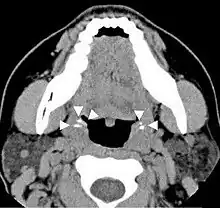

| A tonsillolith lodged in the tonsillar crypt | |

Diagnosis is usually made upon inspection. Tonsilloliths are difficult to diagnose in the absence of clear manifestations, and often constitute casual findings of routine radiological studies.

Imaging diagnostic techniques can identify a radiopaque mass that may be mistaken for foreign bodies, displaced teeth or calcified blood vessels. CT scan may reveal nonspecific calcified images in the tonsillar zone. The differential diagnosis must be established with acute and chronic tonsillitis, tonsillar hypertrophy, peritonsillar abscesses, foreign bodies, phlebolites, ectopic bone or cartilage, lymph nodes, granulomatous lesions or calcification of the stylohyoid ligament in the context of Eagle syndrome (elongated styloid process).[11]